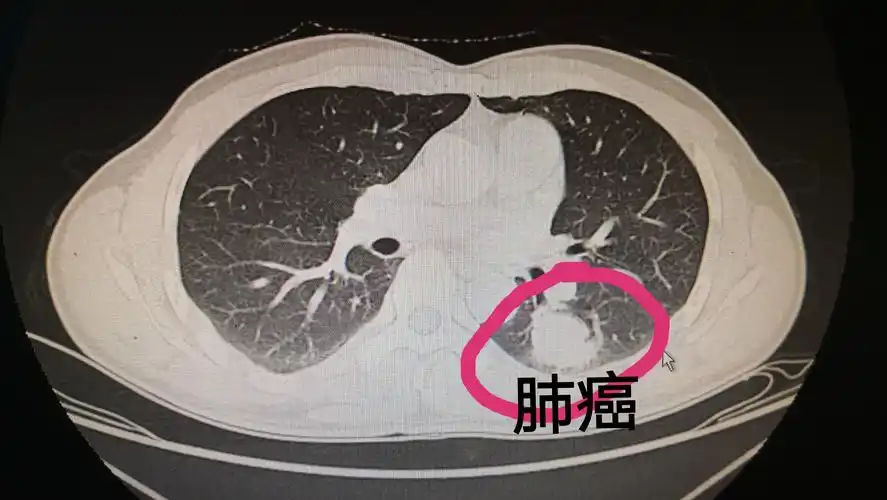

早期肺癌ct图

【读片】肺癌? [病例帖]

胸部x射线 ct增强片 帮帮忙看一下 是肺癌吗?